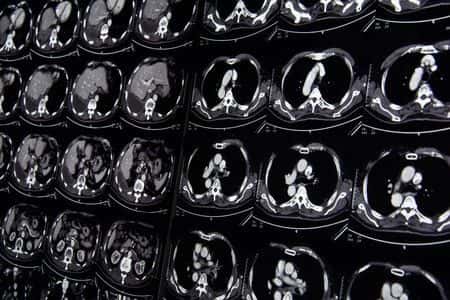

This case involves a female patient who initially wanted to use Essure as a permanent form of contraceptive, but changed her mind and underwent a tubal ligation at a local community hospital instead. The procedure was performed by her private gynecologist and shortly after the procedure, the patient experienced a severe episode of nausea and projectile vomiting. Three days after the procedure, the patient saw her gynecologist who suspected that there was a hematoma in the lower quadrant of the abdomen. The patient was sent back to the hospital where she was admitted for a suspected small bowel obstruction. After being closely followed and treated conservatively with NG tube decompression and slow advancement of a liquid diet, the decision was made to discharge the patient after she had a bowel movement. No scans or confirmatory tests were performed upon discharge. The patient was discharged after a 10-day hospital stay despite the fact that she was continuing to feel ill. Two weeks later, the patient underwent a CT scan for complaints of abdominal pain and the imaging revealed the presence of a hernia. The patient was sent for surgery which identified a significant amount of incarcerated necrotic bowel that was resected due to strangulation.

The diagnosis of an incarcerated hernia is sometimes difficult, but awareness of this entity in the setting of a small bowel obstruction patients should point in this general direction and warrant a detailed examination of the abdominal region, making a prompt diagnosis possible. Additionally, ultrasound is useful in establishing the diagnosis of a hernia and color Doppler studies provide information about the viability of the herniated bowel that is important for surgical planning.